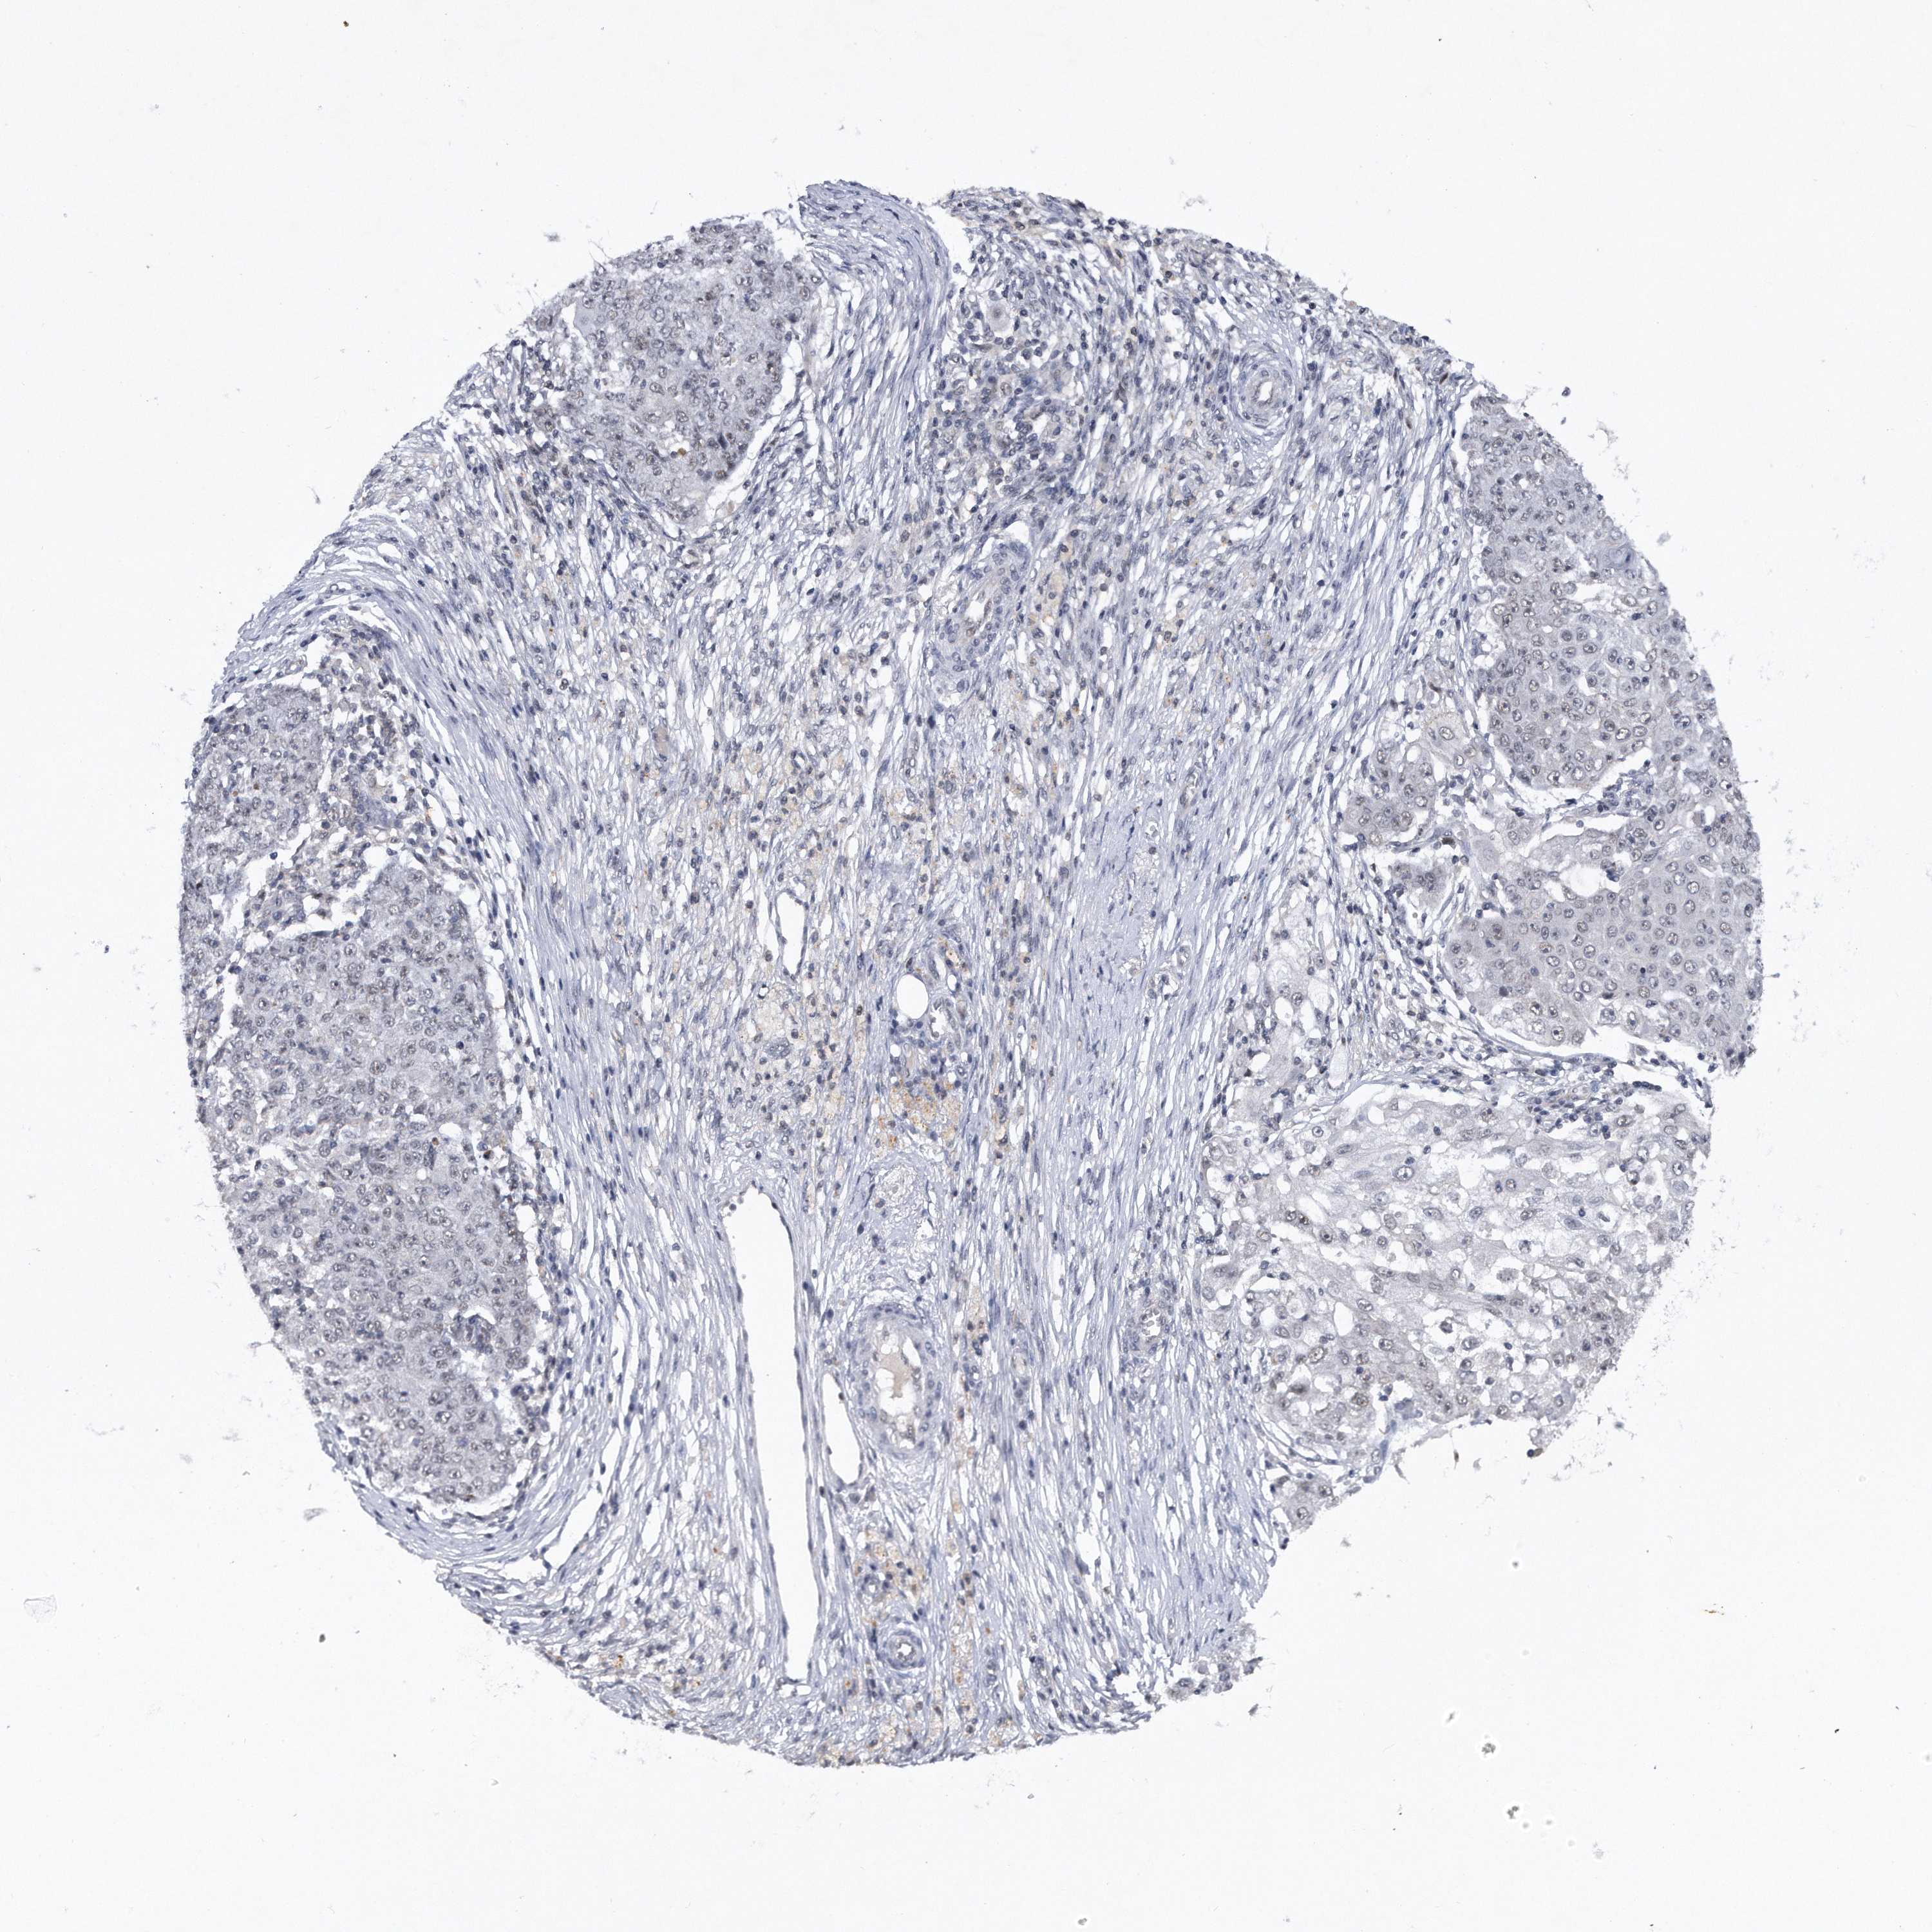

OVARIAN CANCER - Protein expressioni

A mouse-over function shows sample information and annotation data. Click on an image to view it in a full screen mode. Samples can be filtered based on level of antibody staining by selecting one or several of the following categories: high, medium, low and not detected. The assay and annotation is described here.

Note that samples used for immunohistochemistry by the Human Protein Atlas do not correspond to samples in the TCGA dataset.

Antibody stainingi

Antibody staining in the annotated cell types in the current human tissue is reported as not detected, low, medium, or high, based on conventional immunohistochemistry profiling in selected tissues. This score is based on the combination of the staining intensity and fraction of stained cells.

Each image is clickable and will lead to virtual microscopy that enables deeper exploration of all samples and also displays staining intensity scores, fraction scores and subcellular localization as well as patient and tissue information for each sample.

Antibody HPA031530

Staining

High

Medium

Low

Not detected

Intensity

Strong

Moderate

Weak

Negative

Quantity

>75%

75%-25%

<25%

None

Location

Nuclear

Cytoplasmic/membranous

Cytoplasmic/membranous,nuclear

Cystadenocarcinoma, serous, NOS

Carcinoma, endometroid

Cystadenocarcinoma, mucinous, NOS

Carcinoma, NOS